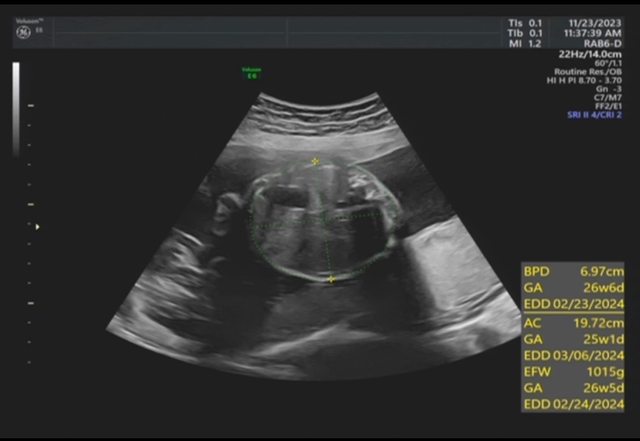

昨天去產檢,醫生覺得寶寶的胃偏大之後要注意觀察 我搜尋了一下好像只有看到胃太小的文,請問大家有沒有遇過類似情況? 我後來看了一下22週的高層次照片,那時候寶寶也是胃大大的,但那時只說是寶寶可能剛 吃飽 https://i.imgur.com/amlKp09.jpg

每一胎的狀況真的不一樣,這次第二胎先歷經羊水少週數小三週,到現在追到剩小一週, 但昨天醫生又提醒胃好像偏大,只希望二寶可以健康平安出生~ -- ※ 發信站: 批踢踢實業坊(www.ptt-site.org.tw), 來自: 101.12.24.40 (臺灣) ※ 文章網址: https://www.ptt-site.org.tw/BabyMother/M.1700797726.A.8D2